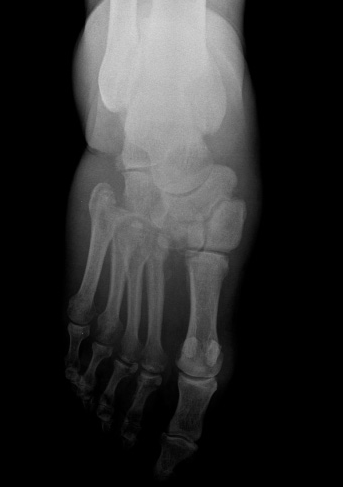

Radiografía de pie diabetico

• Calcificaciones arteriales (arteria pedia, plantar y tibial posterior)

Gas por infección en pie diabetico

Arteria pedia calcificada. Hallazgo bilareral

Alteraciones en tejido óseo

• Infección ósea (osteomielitis)

• Cambios articulares y óseos neurotróficos, con atrofia, reabsorción y necrosis ósea eventualmente.

• Osteopatía diabética

• Neuroartropatia